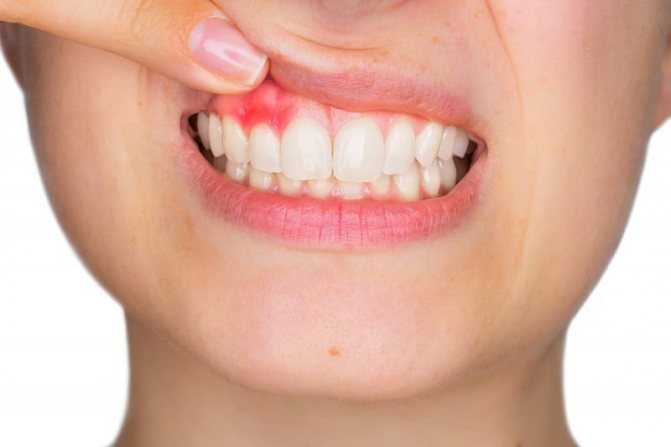

Поэтому с такими неприятными явлениями, как воспаление десен, кровоточивость, сталкивался, наверное, каждый ребенок. К числу заболеваний полости рта относится и ситуация, когда появляется на десне у ребенка какой-то нарост. Данная патология встречается достаточно часто, поэтому родителям важно четко понимать, почему это происходит, как можно справиться с проблемой.

Обычно данный нарост не доставляет человеку болевых ощущений, но он причиняет существенный дискомфорт и нарушает эстетичность, т.к. заметен при разговоре и улыбке. В случае, когда образование запущено или перешло в злокачественное состояние, специфика симптоматики усиливается (все признаки ухудшают общее состояние, они неприятны и довольно болезненны).

Когда люди говорят про нарост на десне, они обычно имеют в виду кисту, которая нередко появляется безо всяких видимых причин. Если нарост не болит при надавливании, то его называют эпулис (или наддесневик). Если его вскрыть, то из нароста выделяется рыхлая масса или вытекает жидкое содержимое. Без своевременной терапии образование рано или поздно само вскрывается, трансформируясь в небольшую опухоль с отверстием на поверхности, из которого свищевой ход идет в толщу кисты. Из образовавшегося свища периодически происходит выделение сукровицы или гноя. При этом общее состояние больного также страдает: его беспокоят головные боли, потеря жизненных сил, а лимфоузлы вблизи очага инфекции (челюстные, шейные или ушные) обычно увеличены и болезненны.